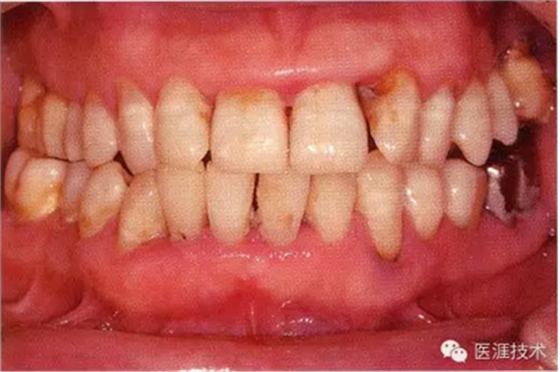

55歲牙周炎男性的臨床照片

55歲男性抽煙患者(1天20支、抽煙35年)。菌斑控制得不好。通過牙周探診,全頜有4~9mm的牙周袋,有1~3度的根分叉部病變。通過X光片觀察,上頜前牙中度牙槽骨吸收,其他地方有中度牙槽骨吸收。受吸煙影響,牙齦纖維性肥厚,呈紅黑色。牙齦幾乎沒有浮腫和發(fā)紅,所以這個病例是從外觀上無法預(yù)測病癥嚴重程度的病例。